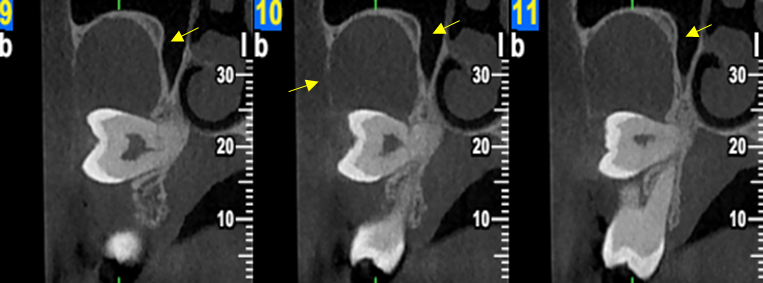

Περίπτωση ιδιαίτερα εκτεταμένης υπολειμματικής κύστης που καταλαμβάνει σχεδόν όλο το δεξιό ημιμόριο της άνω γνάθου εμπλέκοντας και το δεξιό ιγμόρειο άντρο σε γυναίκα ασθενή ηλικίας 75 ετών.

Η κύστη καταλαμβάνει πλήρως τη φατνιακή ακρολοφία στην οπίσθια δεξιά περιοχή της γνάθου και έχει προκαλέσει ιδιαίτερα εκτεταμένη υπέγερση του εδάφους του ιγμορείου άντρου προβάλλοντας εντός αυτού και καταλαμβάνοντας μεγάλο τμήμα της αεροφόρου του κοιλότητας.

Παρατηρείται επίσης ιδιαίτερα εκτεταμένη έκπτυξη και λέπτυνση του πλαγίου τοιχώματος του ιγμορείου άντρου, καθώς και των συμπαγών πετάλων της φατνιακής ακρολοφίας.

Σε αυτές τις περιπτώσεις η Υπολογιστική Τομογραφία Κωνικής Δέσμης (CBCT) μπορεί να βοηθήσει καταλυτικά στη διαφοροδιάγνωση αυτών των βλαβών αλλά και να αποκαλύψει με λεπτομέρεια την έκταση και τα όρια της βλάβης.